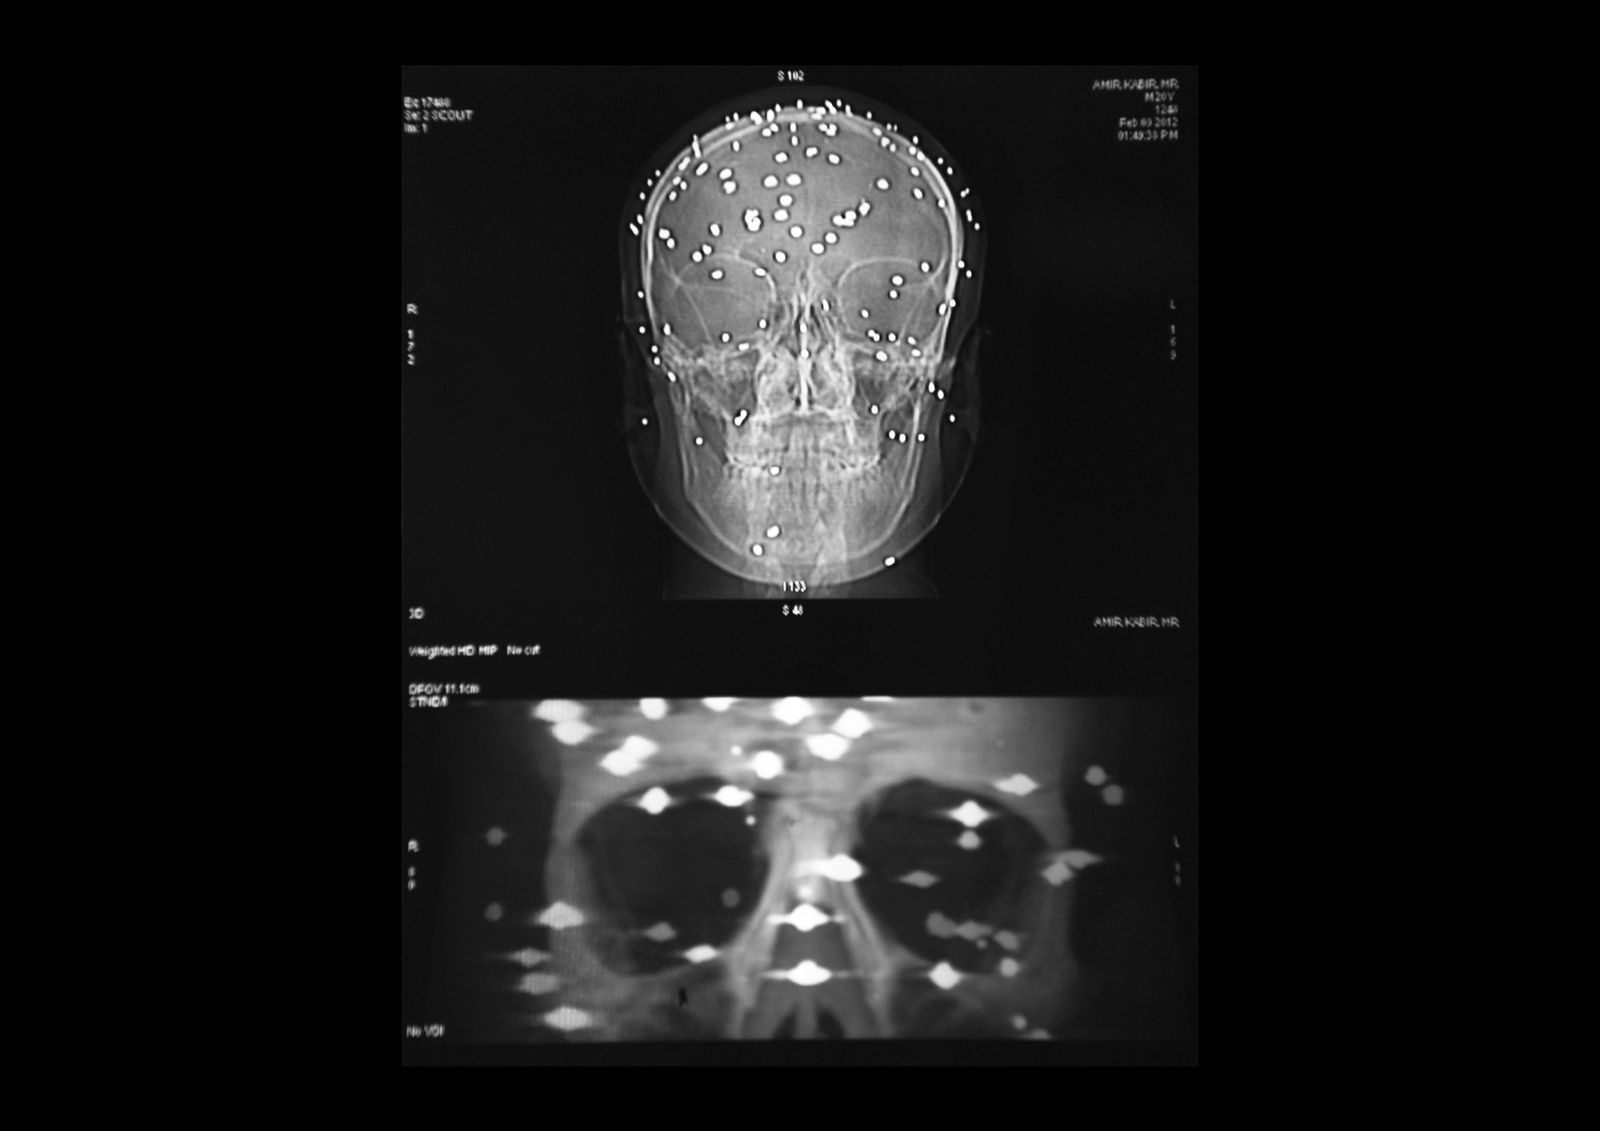

Amir Kabir Beigh, 26 years old, Baramulla. “In September 2010 i was going to buy some medicine for my mother by evening time when a group of security forces fired at me near the bridge of the old town. There had been clashes throughout the day but it was calm at that time. I was alone on the street so only after some minutes somebody found me and took me to the hospital. I have gone through a lot of surgeries all over India but i am still completely blind”. Amir is the first pellet victim of Kashmir, he received hundreds of iron balls on his body.